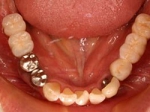

両側5歯症例

両側5歯症例両側5歯症例両側5歯症例 主訴-義歯のバネが壊れて手前の歯が痛んできた。 術前(旧義歯装着、鏡像) 術前(下顎粘膜面、鏡像)術前(下顎粘膜面、鏡像)術前(下顎粘膜面、鏡像) 術前レントゲン術前レントゲン術前レントゲン 術前口腔内(正面観)術前口腔内(正面観)術前口腔内(正面観)

術後(鏡像)術後(鏡像)術後(鏡像) 術後口腔内(正面観)術後口腔内(正面観)術後口腔内(正面観)もう入れ歯は要らなくなりました。 術後レントゲン術後レントゲン術後レントゲン